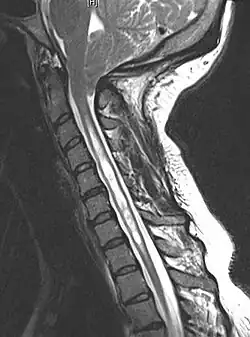

A siringomielia é prontamente diagnosticada com Ressonância Magnética, podendo ou não estar associada à malformação de Chiari.